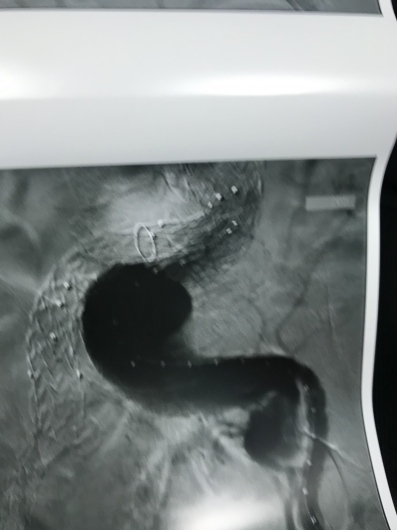

Dirigente Medico di ruolo presso U.O.C. Chirurgia Vascolare ed Endovascolare Ospedale San Giovanni di Dio e Ruggi d’Aragona di Salerno. Pratica attività ambulatoriale, laboratorio di diagnostica ultrasonografica, diagnostica angiografica e attività di sala operatoria (chirurgia open ed endovascolare). L’attività chirurgica tradizionale ed endovascolare comprende il trattamento delle lesioni stenotiche/ostruttive dei tronchi sovraortici (carotidi), lesioni stenotiche/ostruttive delle arterie periferiche e viscerali, degli aneurismi dell’aorta e aneurismi periferici e viscerali (sia in elezione che in urgenza), inoltre l’attività chirurgica comprende il trattamento della patologia venosa (vene varicose/varici) secondo le tecniche chirurgiche classiche (es. stripping) e moderne (laser, radiofrequenza, scleroterapia maggiore), scleroterapia minore di teleangectasie e vene reticolari (estetica vascolare).